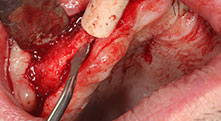

Pourriez-vous décrire brièvement par exemple comment vous procédez pour mobiliser les blocs osseux en vue d’une greffe ?

Pr Bratu : Nous préférons prélever l'os sur la crête oblique externe de la mandibule postérieure, et non dans la région interforaminale. Après l'incision des tissus mous, nous utilisons les nouvelles scies pour définir la quantité d'os à prélever. De la même manière, nous les utilisons également pour la totalité de la préparation dans presque 80 % des cas. Nous avons également parfois recours à d'autres instruments piézoélectriques et, pour terminer, à un burin pour mobiliser le bloc. Nous trouvons cette technique chirurgicale très efficace.